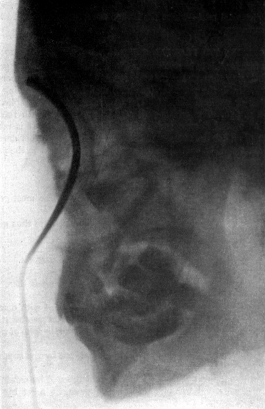

| 267. | Skiagram showing an Angular Tracheotomy Tube in the Trachea | 518 |

| 343. | Radiograph of the Sphenoidal Sinus | 653 |

| 344. | Radiograph of the Sphenoidal Sinus | 653 |